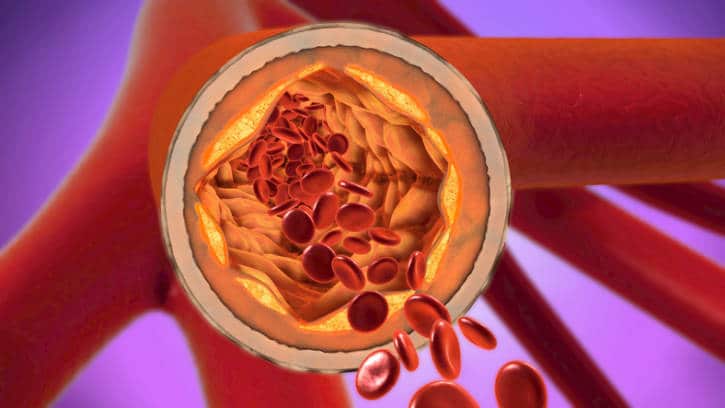

LDL (‘bad”) cholesterol is a type of fat in the blood that contains the most cholesterol. It can contribute to the formation of plaque buildup in the arteries (atherosclerosis). This is linked to higher risk for heart attack and stroke.

HDL (“good”) cholesterol, helps to remove cholesterol from the blood. This keeps plaque from building up in your arteries.